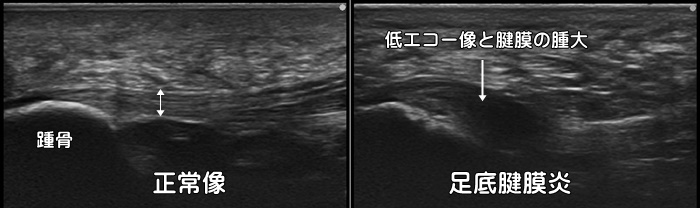

足底腱膜炎

かかとの親指側に着地の際に痛みがあれば足底腱膜炎を疑います。朝の第一歩目の痛み(first step pain)が特徴です。正常な足底腱膜は厚みが4mm未満ですが、足底腱膜炎では4mm以上に肥厚します。また踵骨付着部での腱の肥大が見られます。足底腱膜内にしこりがあれば足底線維腫なども疑います。